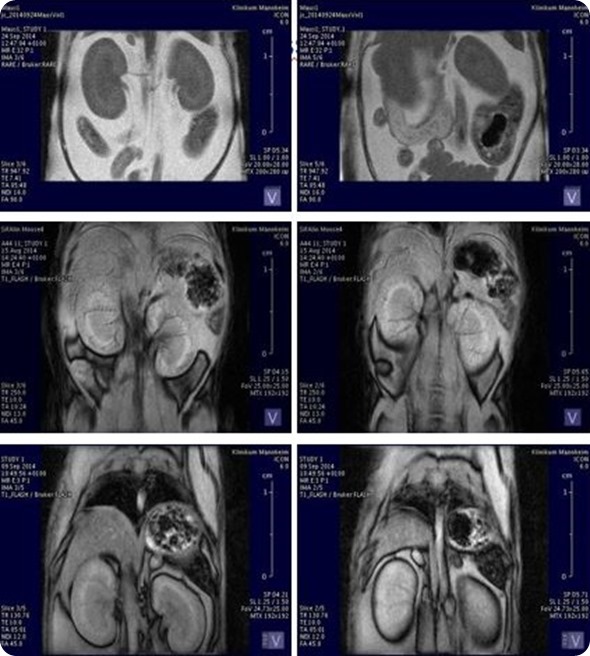

In the case of the MRI, it's mostly a combination with the PET system, which allows a better contrast in the brain or body and enables us to see the soft tissues better or to differentiate better between them in the body.